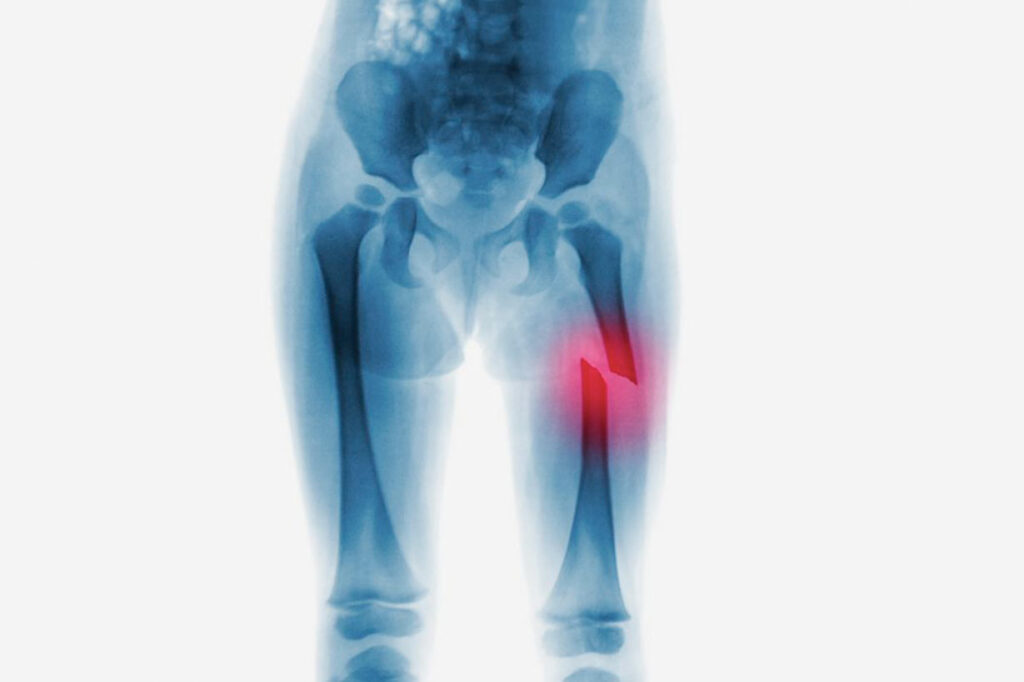

Fratura no fêmur: causas, sintomas e tratamentos

A fratura no fêmur é uma lesão que ocorre por inúmeros motivos. Neste artigo, traremos algumas causas, bem como seus tratamentos. Sobre a fratura O fêmur é o osso mais forte, assim como o mais comprido, por isso, para que ocorra uma fratura, será necessária uma pressão externa muito forte sobre ele, que pode ocorrer […]